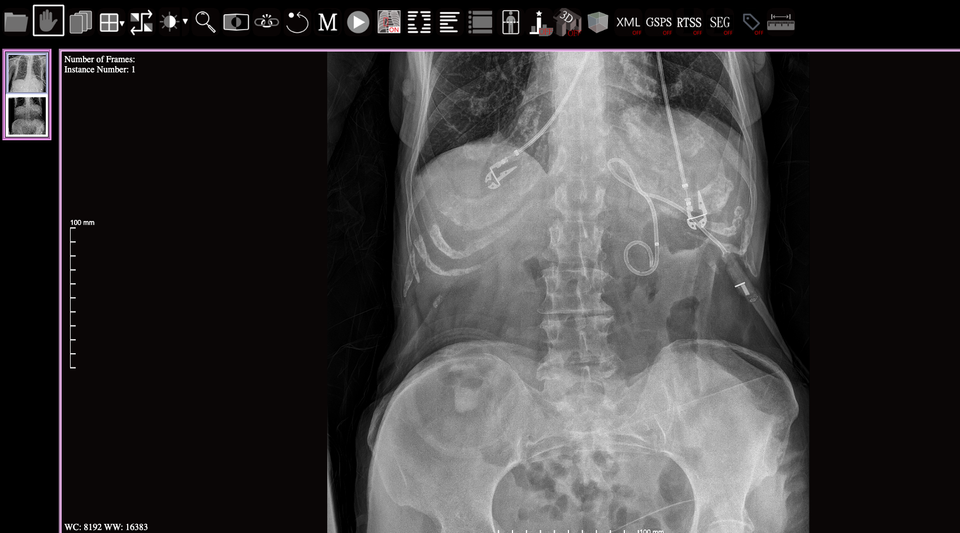

Blue Light is a browser-based medical image viewer is primarily maintained by the Imaging Informatics Labs. It is a pure single-page application (SPA), lightweight, and using only JavaScript and HTML5 technologies so as to deploy it on any HTTP server easily (just put it in HTTP server).

It supports not only opening local data, but also connecting to medical image archives which support DICOMweb. It can display the various image markups and annotations such as Annotation and Image Markup (AIM), DICOM-RT structure set (RTSS), DICOM Overlay, and DICOM Presentation State.

It provides tools for medical image interpretation and 3D image reconstruction, e.g., Multiplanar Reformation or Reconstruction (MPR) and Volume Rendering (VR).